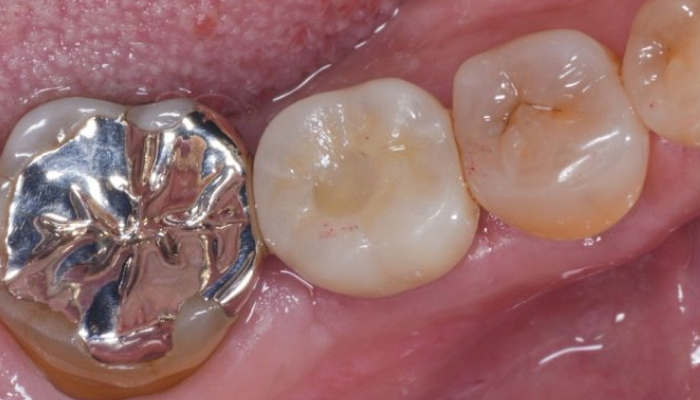

歯を1本失う虫歯や歯周病が原因で、1本の歯を失うことから始まります。特に「第一大臼歯」と呼ばれる一番奥の歯が最初に抜けるケースが多く、それに続いて「第二大臼歯」を失うことが一般的です。この段階では、部分入れ歯やブリッジなどの治療法が選択されることが多いですが、これらの方法は隣接する健康な歯に負担をかける可能性があります。